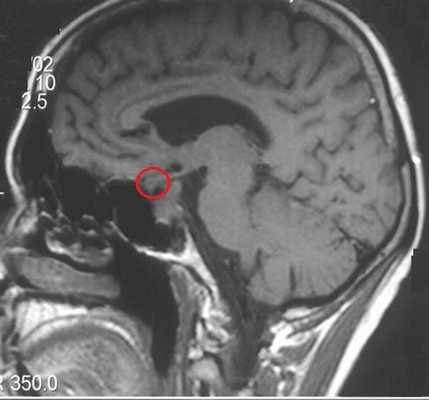

При подозрении на наличие новообразования гипофиза применяют специальный режим сканирования, предусматривающий регулирование толщины сканируемых срезов от 1 мм, небольшое поле зрения, использование контрастного препарата. Благодаря тонкой настройке оборудования и болюсному усилению, микроаденома гипофиза на МРТ определяется на раннем этапе развития. Магнитно-резонансная томография позволяет увидеть образование размером от 3 мм.

Микроаденома гипофиза (указана стрелкой) на снимке МРТ

Микроаденома гипофиза на снимках МРТ имеет ряд характерных признаков:

- неоднородная структура;

- округлая форма;

- очаг имеет гипоинтенсивный сигнал на Т1-взвешенных изображениях;

- выраженная граница, отделяющая образование от здоровых тканей;

- при наличии кровоизлияний и кист наблюдается усиление сигнала на Т2-взвешенных изображениях.

Томограммы позволяют уточнить размеры и расположение очага. При локализации опухоли в турецком седле говорят о эндоселлярной аденоме. Образования, выходящие за пределы костного кармана, называют эндоэкстраселлярными.

Для лучшей визуализации микроаденомы применяют динамическое контрастирование. Метод подразумевает использование короткого временного промежутка, когда велика разница сигналов между новообразованием и участками с нормальной структурой. На снимках МРТ с динамическим усилением аденома гипофиза в первой фазе исследования выглядит как гипоинтенсивный очаг на фоне умеренно контрастирующих здоровых тканей железы.